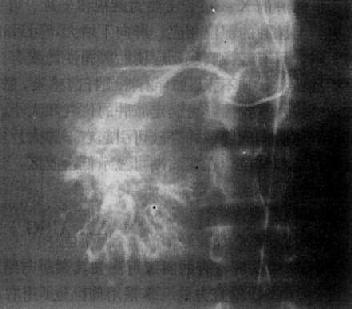

选择性肝动脉影是诊断肝癌的有效方法,它能查出直径小至2cm的肝癌,并确定其范围与数目,供血是否丰富,还可了解有无肝硬化和附近有无肿瘤转移。肝癌的动脉造影可有以下表现:①显示肿瘤血管,表现为肿瘤区内大小不均、形状不规则的血管影或呈“湖样”充盈,其供血动脉增粗;②动脉拉直和移位,动脉边缘不规则且僵硬,系因肿瘤包绕所致;③毛细血管期可见肿瘤染色,呈高密度的结节影;④肝实质期显示为充盈缺损区;⑤有时可形成动静脉瘘,使相邻的门静脉分支早期显影(图4-3-1)。

图4-3-1 原发性肝癌动脉造影

肝动脉造影显示肝内一团巨块状肿瘤血管,大小不均,形态不规则,

其中心呈湖样充盈。供血动脉增粗、迂曲